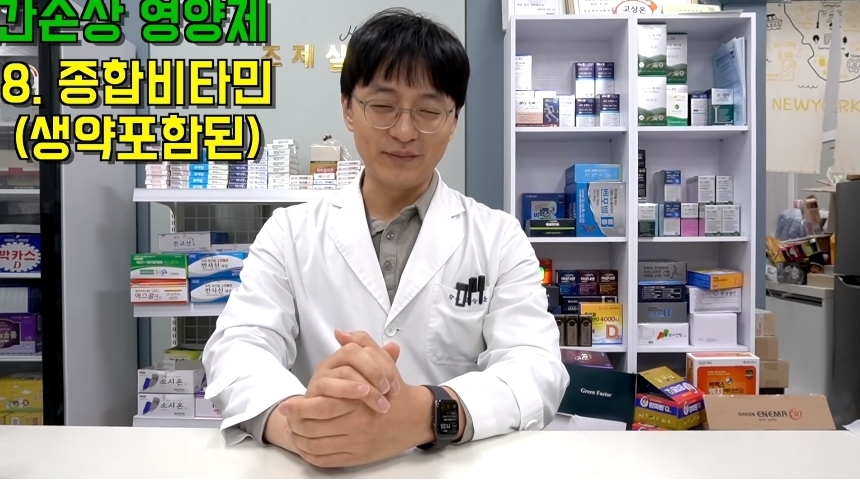

해당 게시물에는 먹으면 오히려 몸에 안좋은 영양제들이 올라왔다.